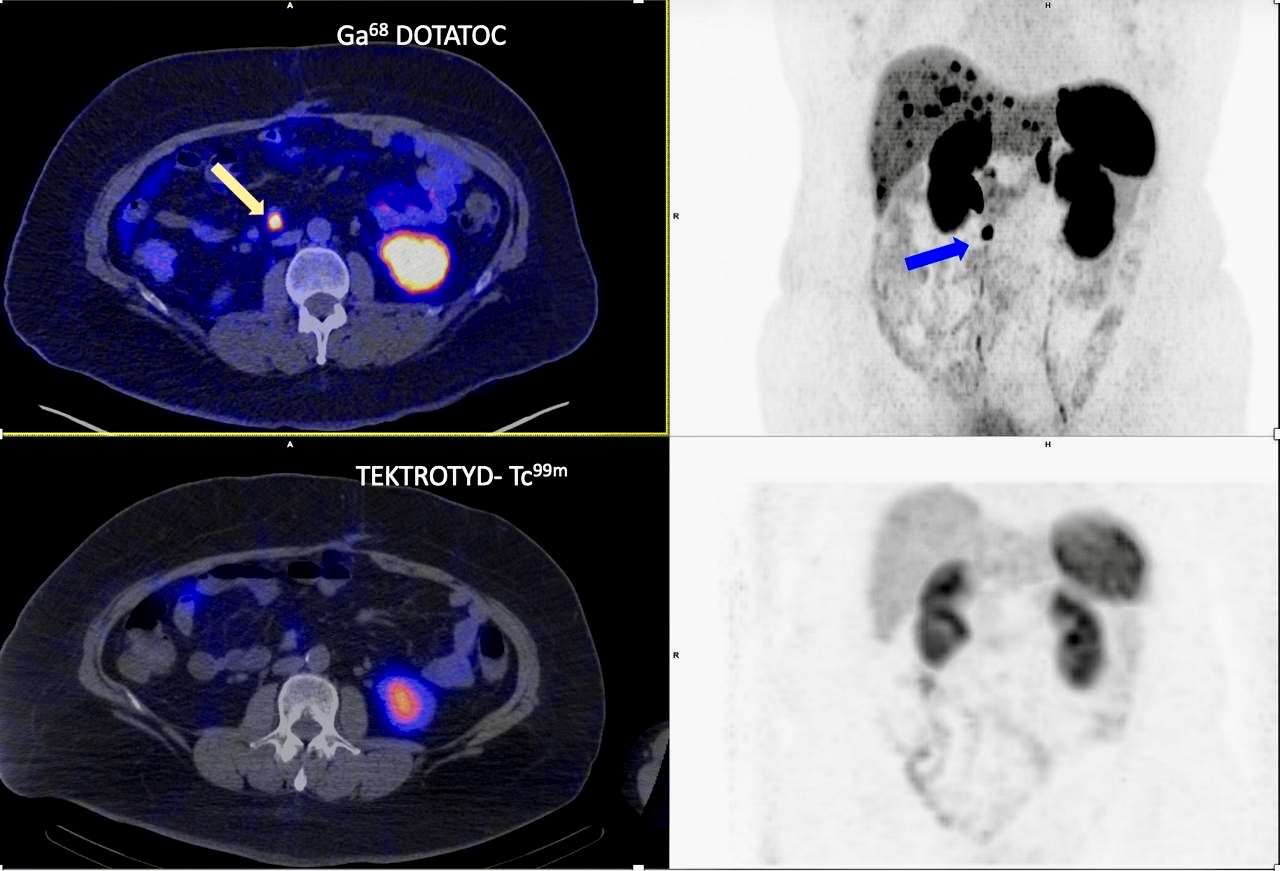

La ponencia no se limitó al terreno mamario. En su parte final, la Dra. Miguel Martínez expuso con especial interés la realización de una cirugía radioguiada con isótopo PET, concretamente con Ga68-DOTATOC, en una paciente con un único implante mesentérico de la misma estirpe tumoral que el primario ya resecado en íleon, correspondiente a un tumor neuroendocrino G1. En este procedimiento se utilizó además una sonda DROP-IN, es decir, la sonda flexible laparoscópica, lo que añade un componente técnico especialmente relevante al caso.

La relevancia de este ejemplo no está solo en el uso del radiotrazador, sino en el contexto clínico en el que se planteó la intervención. La paciente presentaba metástasis hepáticas estables desde hacía más de seis meses y se estaba valorando la posibilidad de trasplante hepático si el PET/TAC de control con Ga68 no mostraba enfermedad extrahepática adicional. Esa combinación entre imagen molecular, selección de pacientes y apoyo a decisiones terapéuticas complejas amplía el alcance de la ponencia y muestra que la cirugía radioguiada puede desempeñar un papel relevante también fuera de sus escenarios más clásicos.